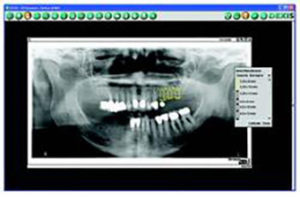

“In the dental emergency situation, you’re squeezing the patient into an already full schedule. You almost always need at least one periapical X-ray to assess the area. Waiting for conventional film development can add 10 to15 minutes to the appointment. With digital, my assistant shoots the radiograph coincident with my walking into the room, and I obtain a specific diagnosis much more rapidly. I end up with a quality emergency appointment that’s five minutes, instead of twenty minutes. My schedule is intact, and my quality of life in the practice is improved.

I also use my digital radiography’s implant software for my implant planning. This tool allows me to precisely calibrate my digital radiographs and select from a comprehensive library of implant models that, once placed on the image, are digitally sized accurately for 2 dimensions (Fig. 4).

Additionally, I can send digital radiographs to a doctor who is seeing the patient at another location the second he calls me, obviously something you can’t do with conventional films.”

Robert C. Fazio, DMD, Norwalk, CT